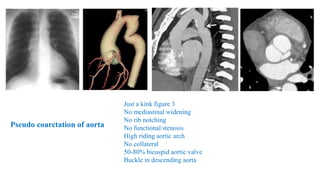

• 30 Y ,F,HYPERTENSIVE

Just a kink figure 3

No mediastinal widening

No rib notching

No functional stenosis

High riding aortic arch

No collateral

50-80% bicuspid aortic valve

Buckle in descending aorta

Pseudo coarctation of aorta